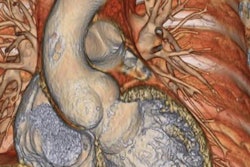

MR studies were performed on a 1.5-tesla scanner (Signa CV/i, GE Healthcare, Waukesha, WI) using a breathhold-segmented k-space cine 2-D FIESTA protocol or a fast GRE protocol. The mean time between MRI and TTE was 118 days.

For both modalities, the aortic root was imaged in the parasternal long-axis plane. Standard measurements were obtained at the aortic annulus, sinuses of Valsalva, sinotubular junction, and proximal ascending aorta. The Bland-Altman analysis was used to assess agreement between TTE and MRI.